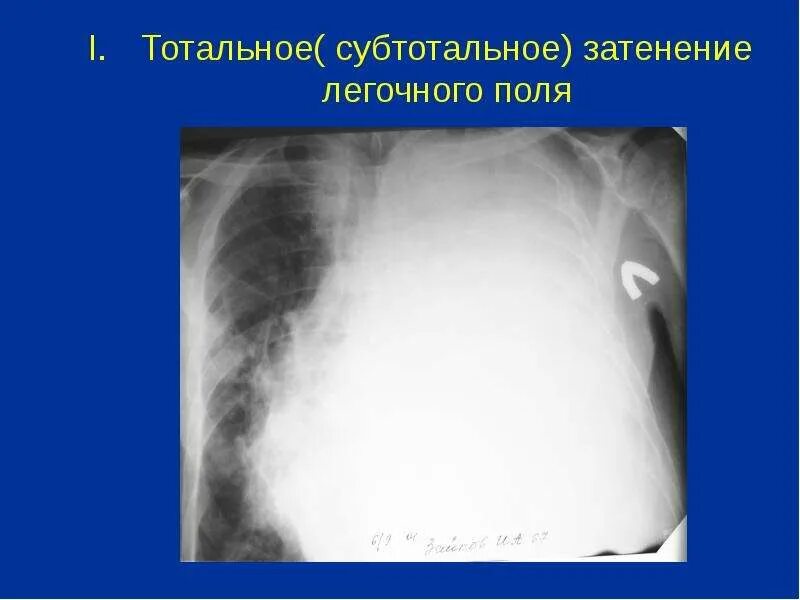

Тотальное отсутствие этоТотальное отсутствие этоТотальное отсутствие этоТотальное и субтотальное затемнение легочного поля. синдром тотального затемнения легочного поля. синдром тотального и субтотального затемнения легочного поля. синдром тотального, субтотального легочного затемнения.Тотальное отсутствие этоТотальное отсутствие этоТотальное отсутствие этоТотальное отсутствие этоТотальное да. техника тотальное да. техника тотальное да примеры.Тотальный ателектаз рентген. ателектаз правого легкого рентгенограмма. тотальный ателектаз легкого. тотальное затемнение ателектаз.Тотальное отсутствие этоСиндром затемнения легочного поля рентген. рентген тотальное затемнение легкого. синдром обширного затемнения легочного поля рентген. синдром тотального затемнения легочного поля.Тотальное и субтотальное затемнение легочного поля. субтотальное затемнение легких.Безопасность это отсутствие опасности.Тотальное отсутствие этоСиндром тотального затемнения легочного поля. тотальное и субтотальное затемнение легочного поля. субтотальное затемнение легких рентген. обширное затемнение легочного поля.Гомогенное затемнение легкого что это такое. симптом тотального затемнения. тотальное затемнение смещение средостения в противоположную сторону.Тотальное и субтотальное затемнение легочного поля. субтотальное затенение легочного поля. синдром тотального затемнения легочного поля. синдром субтотального затемнения легочного поля.Тотальное отсутствие этоТотальное отсутствие этоТотальное отсутствие этоТотальное затемнение легочного поля. гомогенное затемнение. тотальное гомогенное затемнение левой.Тотальное отсутствие этоТотальное отсутствие этоТотальное отсутствие этоТотальное отсутствие этоЗдоровье это отсутствие болезней. здоровье это отсутствие болезней нормальное функционирование. нормальное функционирование организма. здоровье это отсутствие болезней и физических недостатков.Тотальное отсутствие этоЗдоровье это не только отсутствие болезней. отсутствие болезней.Тотальное да. техника тотальное да. тотальное да в психологии. техника тотальное да примеры.Тотальное отсутствие этоТотальное отсутствие этоПрогул это отсутствие на рабочем месте без уважительной причины. отсутствие на работе без уважительной причины. отсутствовал на рабочем месте без уважительной причины. прогул это отсутствие на работе без уважительных причин.Отсутствие деятельности. равенство это отсутствие.Тотальное отсутствие этоТотальное отсутствие этоТотальное отсутствие этоТотальное отсутствие этоТотальное отсутствие этоТотальное затемнение легкого со смещением средостения. тотальное затемнение легочного поля. тотальное и субтотальное затемнение легочного поля. синдром смещения средостения.